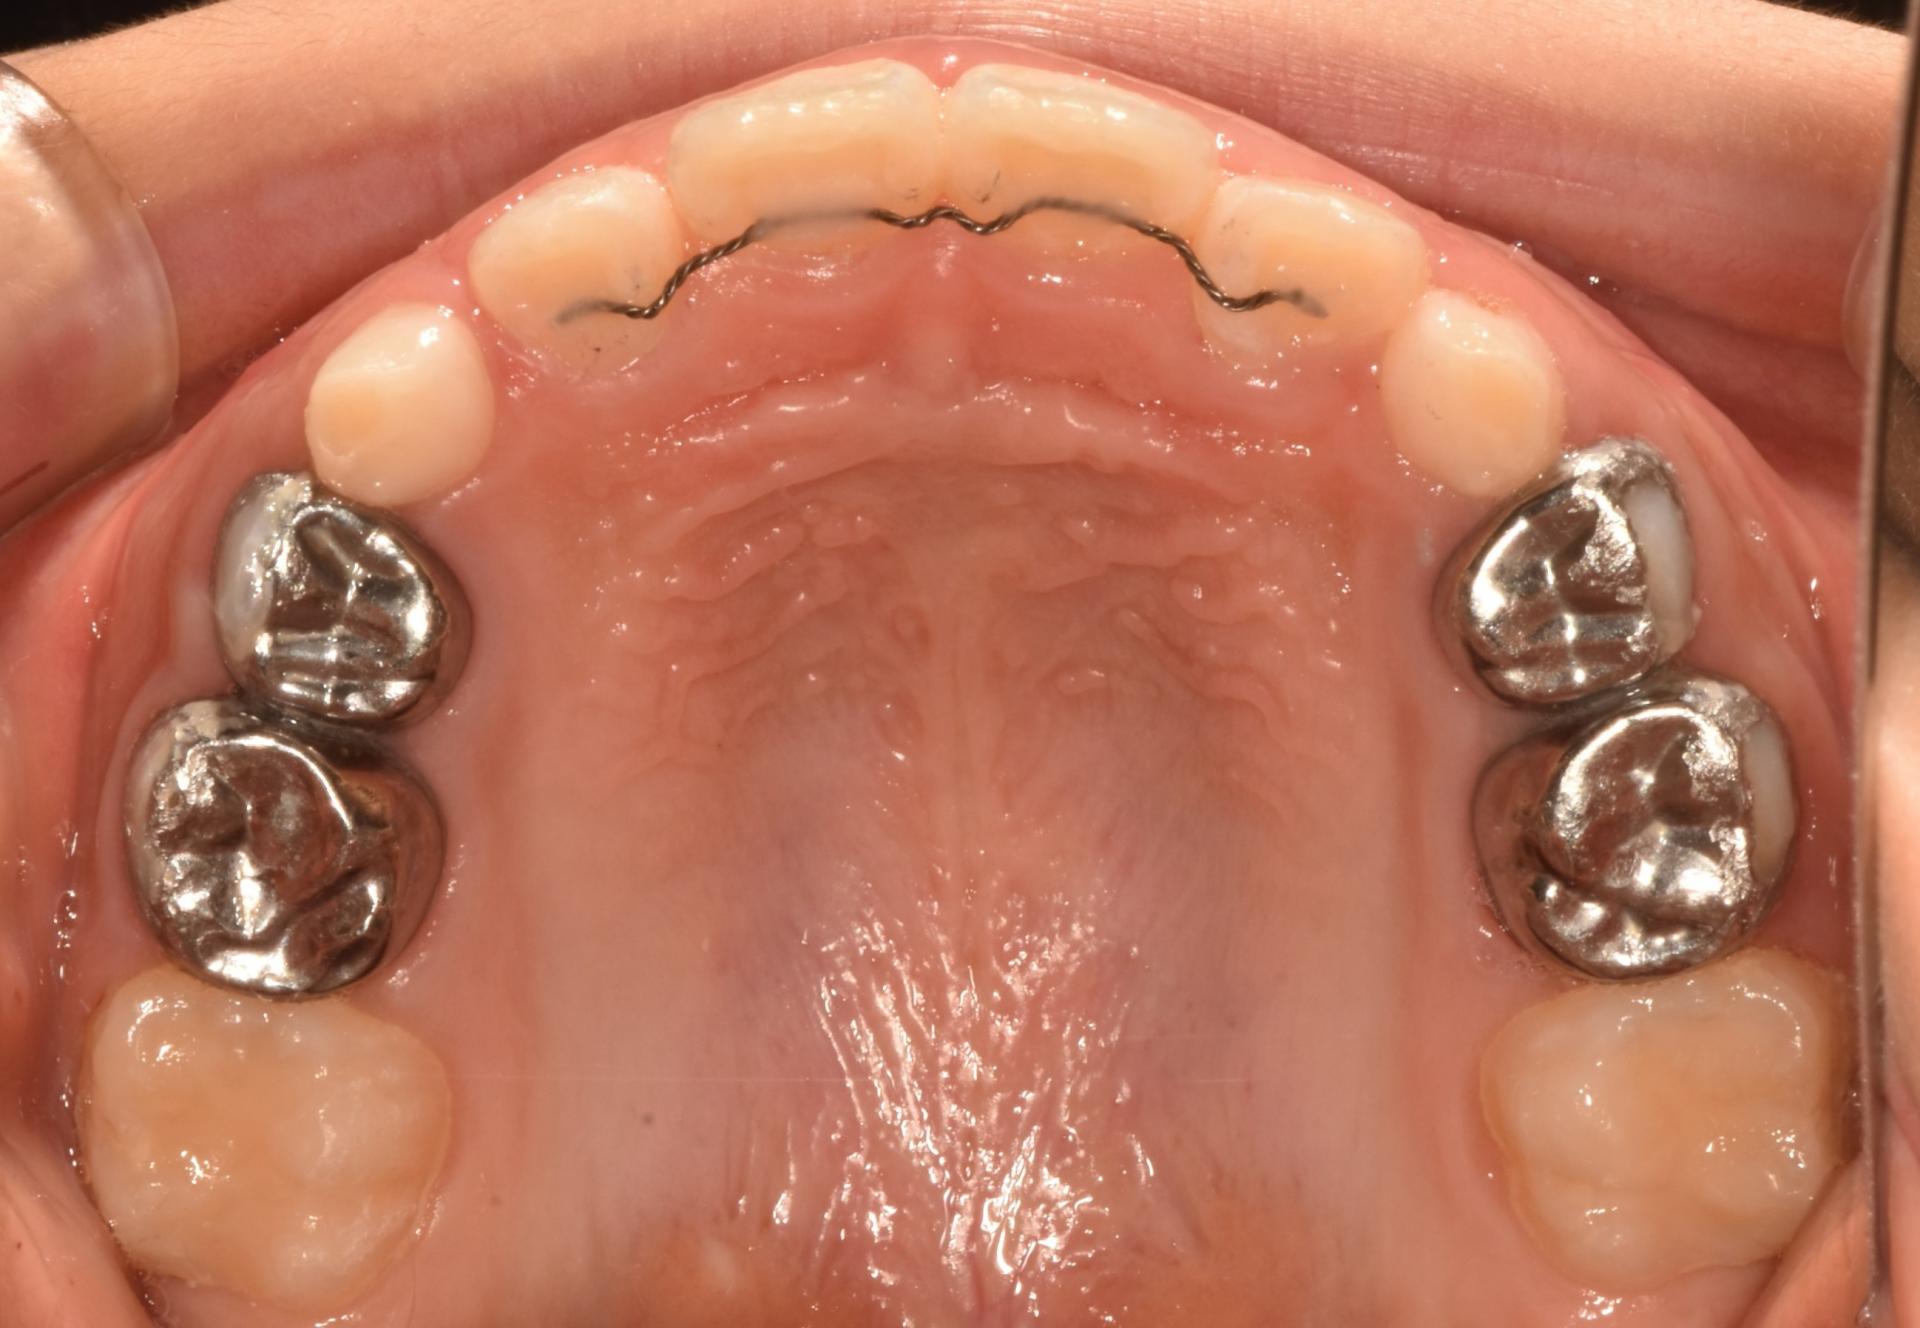

치료완료 후의 모습입니다. 앞니도 가지런해졌고, 좁았던 악궁이 넓어져서 추후 나올 송곳니, 어금니의 공간도 충분합니다.

치료개시일 : 2024.02.16. 치료종료일 : 2024.09.09. |

치료개시일 : 2024.02.16.

치료종료일 : 2024.09.09.